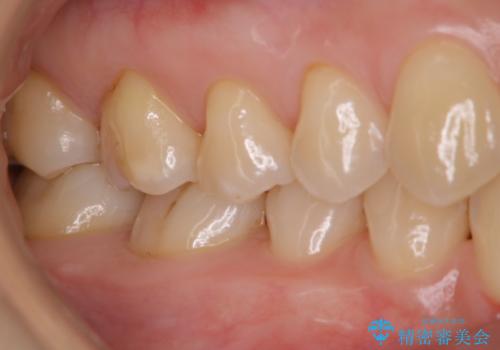

- 毎日歯磨きをしているのに、奥歯のザラつきが気になるとのことでした。プラーク・歯石・ステインが付着していたためPMTC60分コースを行いました。

PMTCとは、【プロフェッショナル・メカニカル・ティース・クリーニング】です。

毎日の歯磨きだけでは、落としきれない汚れや、プラークの元となるバイオフィルムという細菌の膜を専門の機械や材料を使用して除去することです。これらの処置を行うことで、虫歯・歯周病・口臭予防などになります。

また、汚れを除去することでご自身本来の歯の表面となり、歯磨きだけでは得られないツルツル感と、全体的に明るい印象に仕上がります。